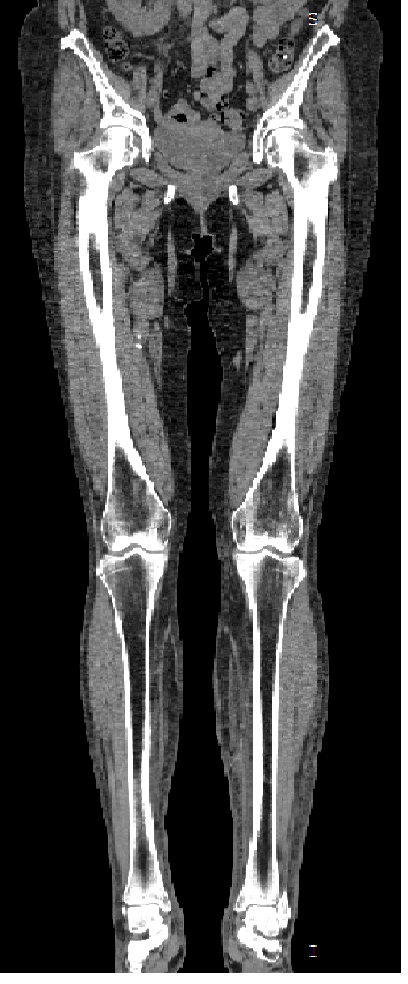

Мультиспиральная компьютерная томография является современным лучевым методом исследования, который позволяет с помощью рентгеновского излучения получить посрезовые снимки и после цифровой обработки создать объемные модели исследуемой области в мельчайших подробностях. Рентгеновские лучи в большей степени поглощаются плотными тканями организма, поэтому на снимках хорошо визуализируются кости скелета. Для более детальной оценки состояния мягкотканных структур зачастую проводится контрастное усиление.

В наших медицинских центрах КТ мягких тканей конечностей выполняется на современных мультиспиральных компьютерных томографах экспертного уровня TOSHIBA AQUILION. Аппараты послойно сканируют область исследования, одномоментно выполняя множество тончайших срезов. В результате получаются снимки высокого качества и трехмерные модели с изображением костного скелета и мягких тканей конечностей. При этом методика скоростного мультисрезового сканирования обеспечивает минимальную дозу рентгеновского облучения для пациента.